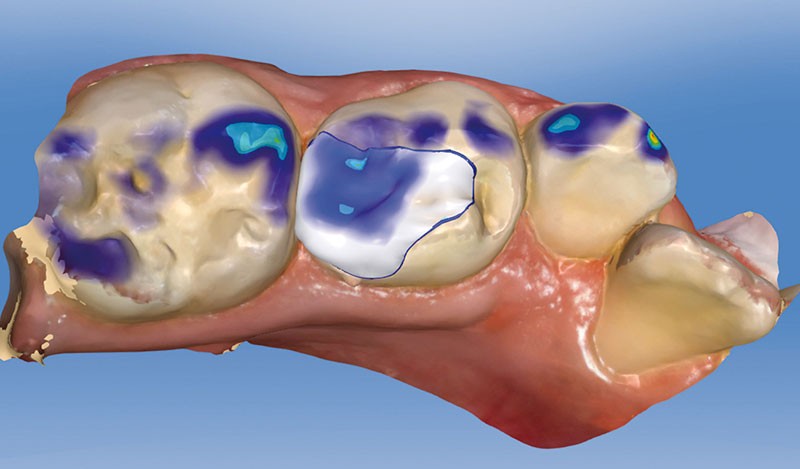

Lors d’une perte de substance étendue et/ou après une pulpotomie sur dent temporaire, il est classiquement réalisé une coiffe pédodontique préformée métallique pour assurer une restauration pérenne. Cette technique fiable et simple n’en demeure pas moins délabrante (fig. 1) et inesthétique (fig. 2).